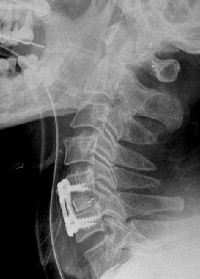

Cage + plaque en C5C6

Radiographie postopératoire

L’intervention se fait sous anesthésie générale le plus souvent.L’incision cutanée droite ou gauche, horizontale ou verticale, sera choisie par votre chirurgien et ne correspond pas toujours au côté de la douleur. Le patient opéré est en général couché sur le dos en position demi-assise, après avoir repéré le niveau à opérer par contrôle radiographique ou radioscopique.

Qu’il s’agisse d’ostéophytectomie transdiscale ou de corporectomie, une fois le canal cervical libéré, il faut restabiliser la colonne vertébrale et restituer la courbure et la hauteur du segment de colonne opéré. Le chirurgien pourra là utiliser diverses techniques : greffon osseux prélevé sur votre crête iliaque (os du bassin), geste nécessitant une incision supplémentaire, greffon de substitut osseux (il en existe plusieurs variétés), cage artificielle placée entre les corps vertébraux, très souvent une ostéosynthèse est ajoutée par plaque métallique vissée ou agrafe spéciale. Ces matériaux métalliques sont de nos jours le plus souvent en titane, métal qui ne perturbe pas (au contraire de l’acier inox) le contrôle post-opératoire par IRM ou scanner.

Le risque de phlébite est exceptionnel en raison d’un lever précoce, et il n’est habituellement pas nécessaire de mettre en place un traitement anticoagulant postopératoire. Les fils ou agrafes cutanées sont enlevés entre cinq et dix jours postopératoires. Une radiographie postopératoire est réalisée, soit en salle d’opération soit en cours de l’hospitalisation.